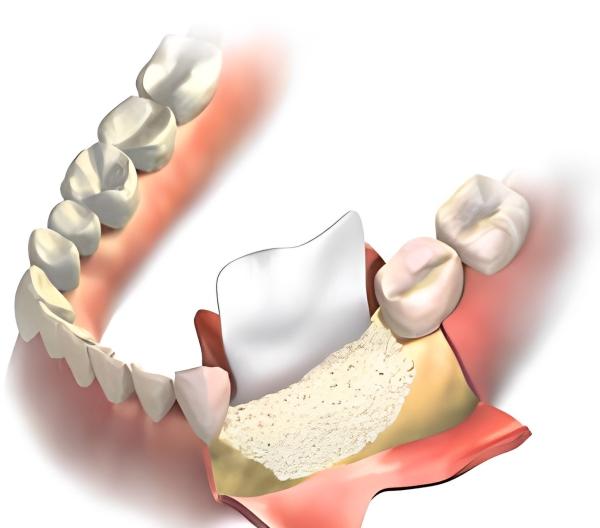

Bước 3: Thực hiện ghép xương

Bác sĩ rạch một đường nhỏ ở nướu để lộ xương hàm, sau đó đưa vật liệu ghép xương vào vùng bị khuyết thiếu. Trong nhiều trường hợp, bác sĩ sẽ sử dụng thêm màng collagen (màng sinh học) để che phủ vùng xương ghép, giúp cố định vật liệu và ngăn nướu phát triển quá nhanh vào vùng xương.